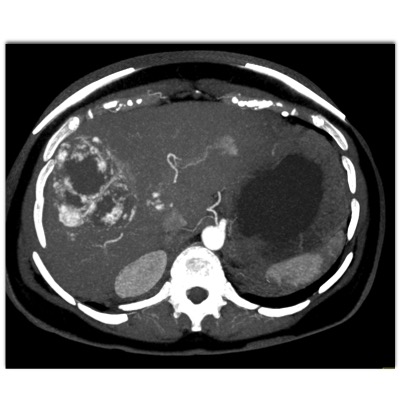

The most likely diagnosis in this case is?

hepatoma

hepatic adenoma

MCN (mucinous cystic neoplasm)

hemangioma